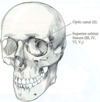

What is this top arrow pointing to? What N passes through here, and what is its function?

- Optic canal: CN II (optic N)

- Carries visual info from retina of the eye back to the brain, allowing for vision

What is this bottom arrow pointing to? What N passes through here, and what is its function?

- Superior orbital fissure: CN III (occulomotor), CN IV (trochlear), V1 (ophthalmic of CN V), CN VI (abducens)

- CN III: controls orbital mm of the eye (except supraoptic and lateral rectus), and carries fascicle of NN that constrict the pupil

- CN IV: controls supraoptic mm of the eye

- CN VI: controls lateral rectus mm of the eye

- V1: transmits sensory info from ipsilateral forehead and scalp to brainstem

Identify/name the bony openings through which the cranial nerves exit the skull.

- Cribiform plate: olfactory bulb fibers pass through here to reach nasal epithelium; trauma may shear these fibers to produce anosmia

- Optic canal: optic nerve (CN II)

- Superior orbital fissure: CN III, IV, VI, and V1

- Foramen rotundum: V2 (maxillary branch)

- Foramen ovale: V3 (mandibular branch)

- Foramen spinosum: middle meningeal artery

Internal auditory canal/meatus: CN VII (facial) and CN VIII (vestibulocochlear)

1. Facial exits via stylomastoid foramen

2. CN VIII leaves via external auditory meatus -

Jugular foramen: CN IX (glossopharyngeal), X (vagus), XI (spinal accessory)

1. Spinal branches of CN XI pass rostrally through foramen magnum, join cranial branches, and exit via the jugular foramen - Hypoglossal canal: CN XII (hypoglossal)